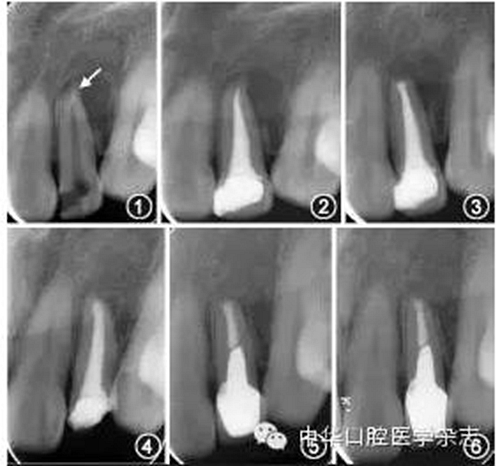

常用的非手術(shù)治療方法包括采用顯微超聲技術(shù)從根管內(nèi)取出分離器械、在分離器械側(cè)方形成旁路通過、或?qū)⒎蛛x器械保留于根管內(nèi)作為部分根充物。對于非手術(shù)治療無法取出分離器械的病例,若根管內(nèi)殘余感染導致癥狀持續(xù)或加重,在充分評估療效和風險后可以考慮行顯微根尖手術(shù),圖1~6為1例顯微手術(shù)處理根尖段分離器械的病例,術(shù)后31個月復(fù)查顯示根尖愈合良好。術(shù)前拍攝錐形束CT可以獲得分離器械位置、根尖炎癥范圍、術(shù)區(qū)與鄰近重要解剖結(jié)構(gòu)間的距離等信息;術(shù)中暴露根尖后,根據(jù)分離器械的位置和長度,可以將分離器械與根尖一并截除,或切除根尖后取出器械。

圖1 術(shù)前根尖X線片示22根尖段分離器械(箭頭)伴根尖周陰影 圖2 22完成根管治療,分離器械暫未處理 圖3 22顯微根尖手術(shù)后根尖X線片示根尖切除和倒充填,術(shù)中已去除分離器械 圖4 術(shù)后14個月復(fù)查,22根尖陰影較術(shù)前縮小 圖5 術(shù)后16個月復(fù)查,22根尖陰影進一步縮小,完成冠修復(fù) 圖6 術(shù)后31個月復(fù)查,22根尖愈合良好